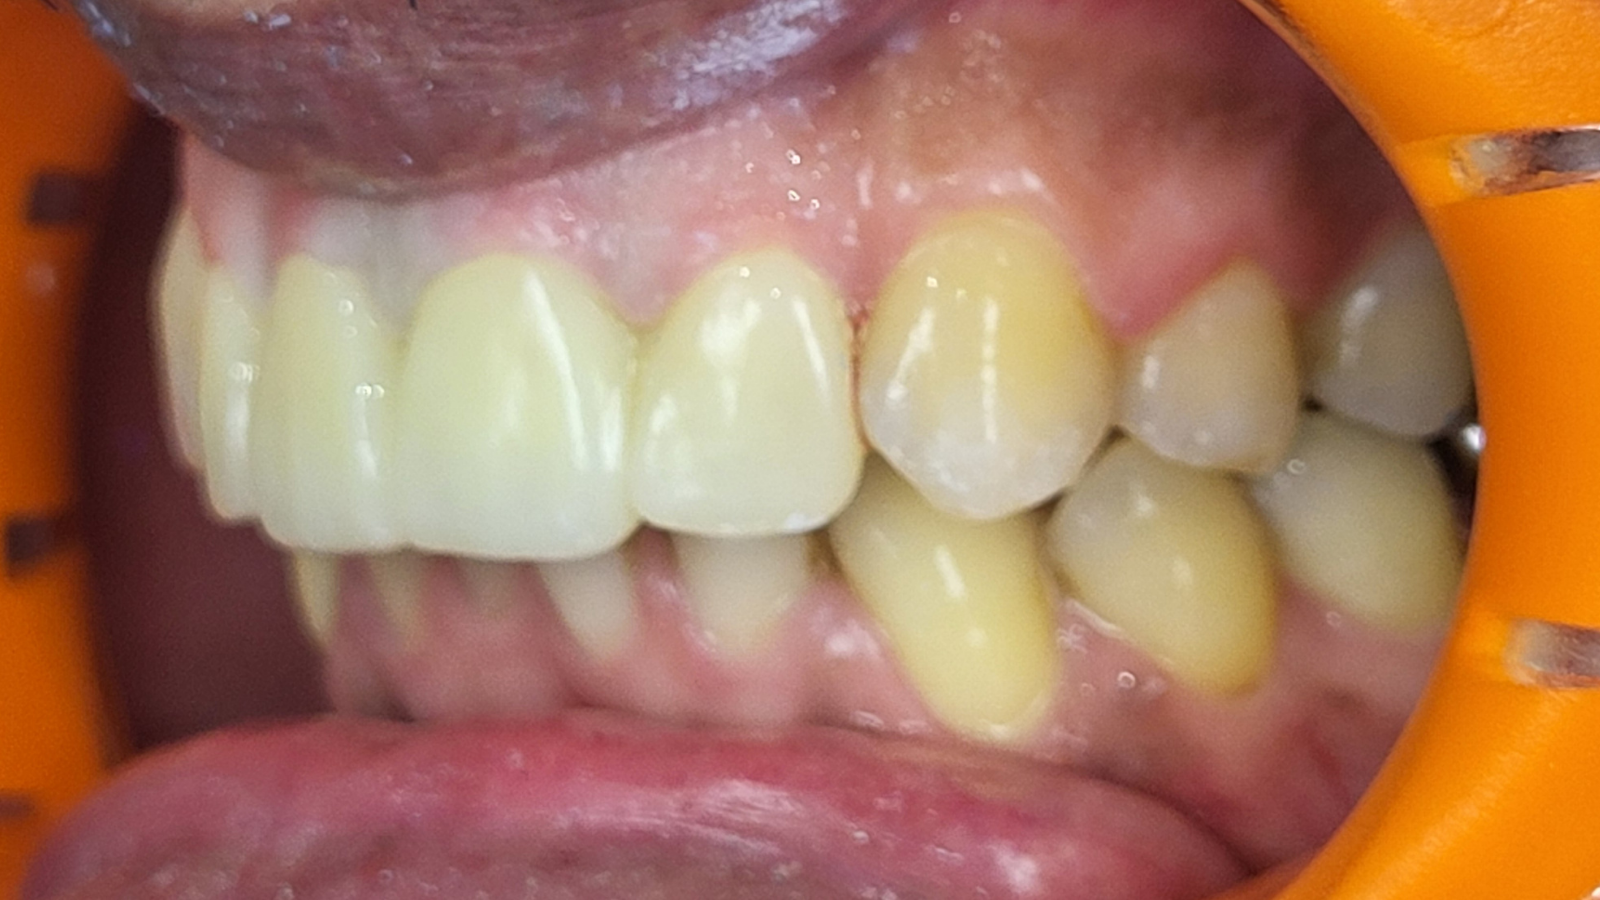

Réhabilitation complète avec mise en charge immédiate (4 implants bas / 6 implants haut)

Le patient se présente avec des dents qui bougent, en haut et en bas.

Nous avons commencé par la mâchoire inférieure avec 4 implants et une mise en charge immédiate.

Trois mois après, le haut a été fait avec le même principe avec 6 implants.

Cette fois-ci, il existait un déficit osseux, résolu par une technique d’expansion sans avoir recours à la greffe d’os.

Les prothèses réalisées sont vissées, ce qui permet de les enlever, les nettoyer une fois par an, ou résoudre n’importe quel problème.